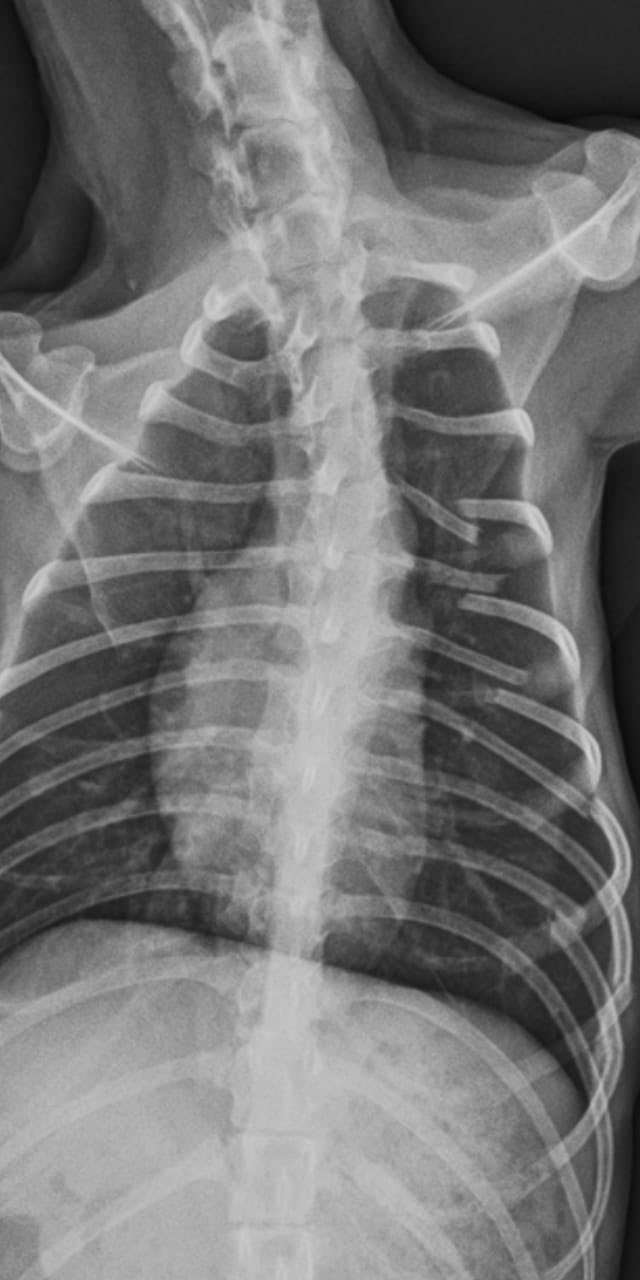

El joven será indagado por maltrato animal. Mía tiene seis costillas rotas y una lesión en la cadera.

La agresión se dio en el contexto de una pelea con su ex novia. Si bien ella aclaró que nunca ejerció violencia contra ella, tras la discusión y por la frustración descargó su furia con el inocente animal que sufrió quebraduras en seis costillas además de una grave lesión en la cadera.